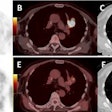

Radiotherapy boost based on PET not always helpful